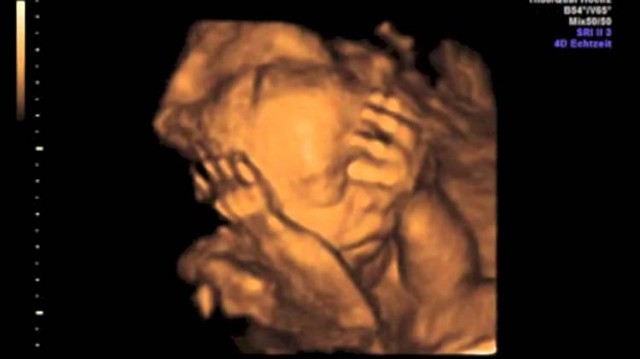

Embriyo transfer aşamasında, laboratuvar şartlarında döllenmiş yumurtanın gelişmesiyle elde edilen embriyo, kadının rahmine transfer ediliyor. Fakat, rahimde o anda kasılmalar olursa bu, embriyonun rahme tutunabilme, dolayısıyla gebelik oluşması ihtimalini, olumsuz etkileyebiliyor.

Araştırma, hipnoterapinin kadınların transfer anında rahatlamasına yardım edebileceği ve tedavinin başarı şansını arttırabileceği düşüncesinden hareketle yapıldı. Tüp bebek tedavisi gören kadınlar öncelikle hipnotize edilmeye uygunlar mı buna bakıldı. Embriyoları transfer edilirken, kadınlardan 89’u hipnotize edildi. Kadınlardan bazıları daha önce de bir ya da birden fazla tüp bebek tedavisi görmüştü.

Hastalar için embriyo transferi stresli bir an olarak bilinir, hatta bu anın tüm tedavi sürecinde stresin tavan yaptığı an olduğu söylenebilir. Hipnozun kişi üzerindeki sakinleştirici etkisi tüp bebek tedavisinin başarılı sonuçlanmasına olumlu katkı yapıyor. Ayrıca hasta hipnoz altındayken yapılan embriyo transferi klinik gebelik oranına ciddi katkı yapıyor.